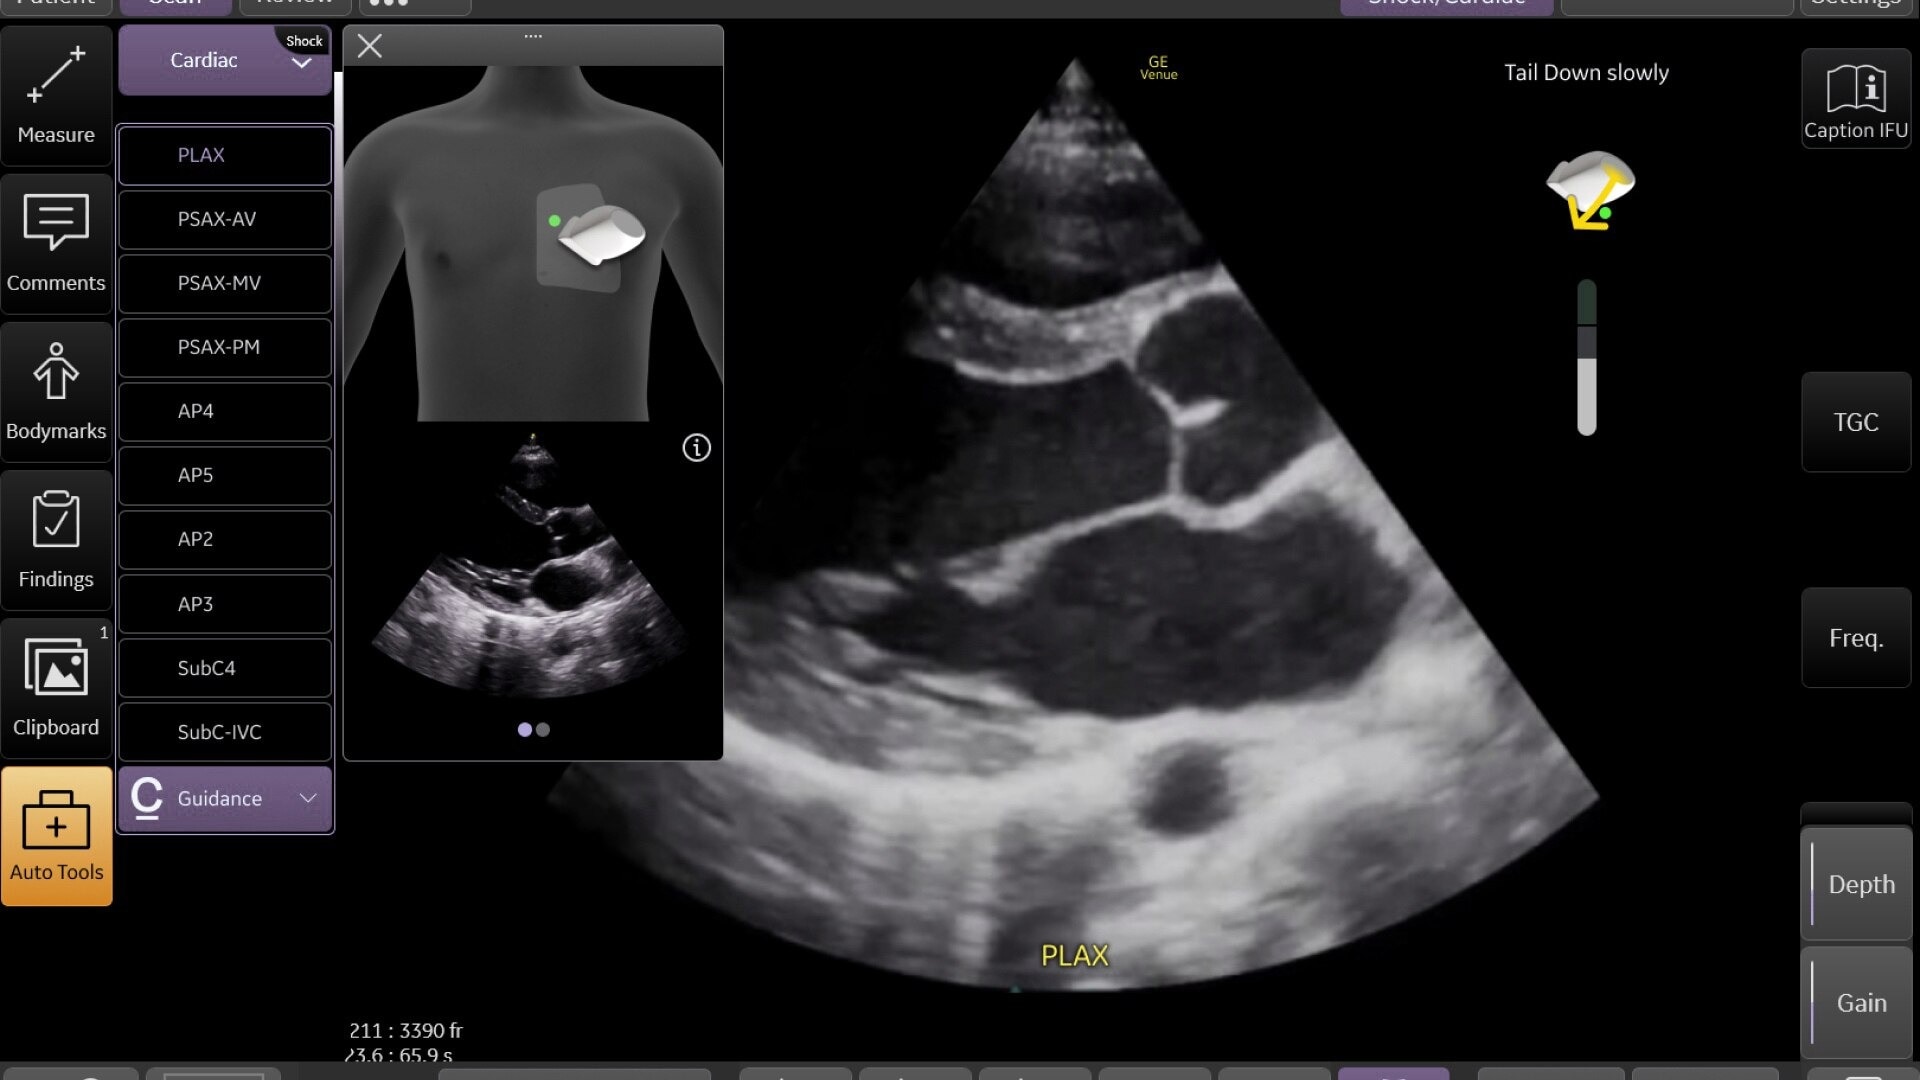

Venue Sprint™ gives you the uncompromised image quality and smart workflow of Venue™ family systems along with the freedom and maximum portability of wireless probes. This all-in-one, entry-level solution combines wireless connectivity with a small, streamlined console. It features Venue family software, to give you access to the AI tools you need, to simplify advanced exams whenever and wherever care is needed.

With the portability and mobility to go anywhere, you can get ahead with Venue Sprint. Take handheld ultrasound to different clinical spaces, sync up and be ready to go. Venue Sprint supports a wide range of environments including:

Enables on-the-spot visual confirmation, aiding the team in decision-making and collaboration on complex cases.

Enables assessments for a variety of anatomy all with a single device. Supports deep and shallow scanning with seamless data connectivity.